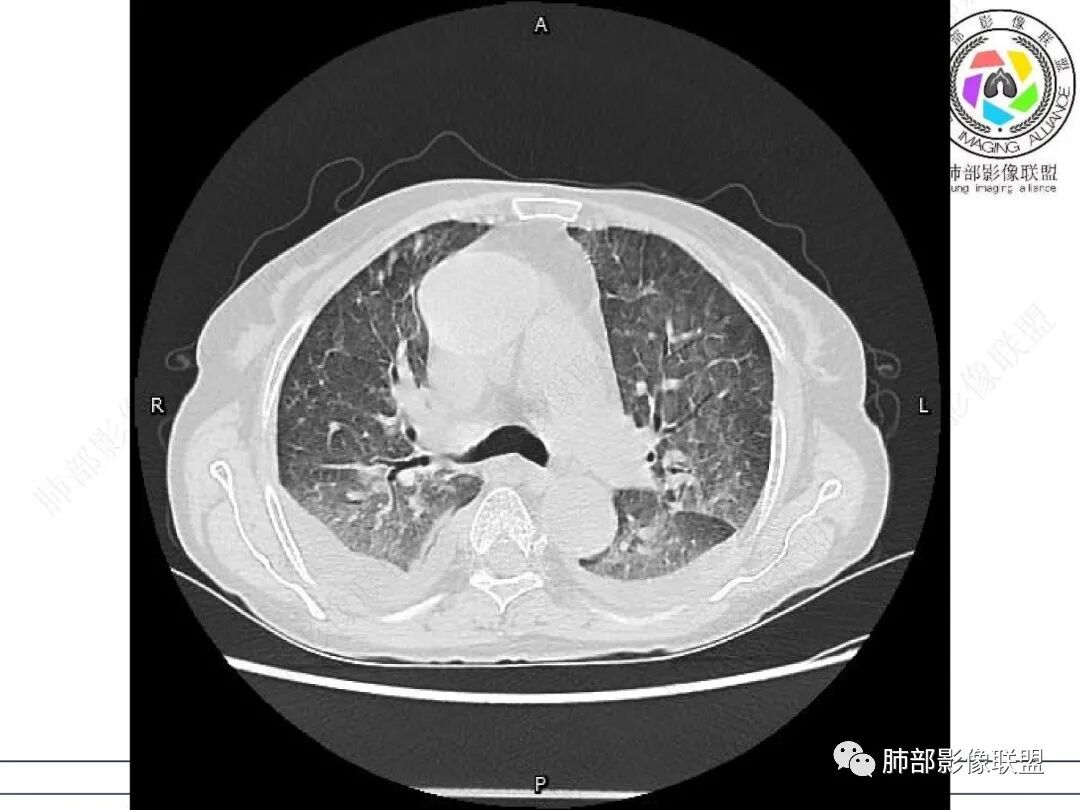

心脏大,胸腔积液,小叶间隔增厚,双肺磨玻璃影,考虑存在肺水肿,另双肺间质性炎性,类风关病史,考虑CTD-ILD,左肺上叶结核可能。

两肺叶后肋膈角区见多发蜂窝状结构破坏表现,双肺叶小叶间隔增厚,左肺上叶后段及舌段和右肺中叶胸膜炎性肉芽肿特点,双侧胸腔少量积液,有类风湿性关节炎治疗史,结缔组织相关性间质性肺病。

发热,有类风湿性关节炎、糖尿病基础病,长期口服激素及免疫抑制剂,双肺多发磨玻璃影及小叶间隔增厚,蜂窝影,支气管扩张考虑非特异性间质性肺炎存在,左肺上叶不规则结节影,周围长毛刺局部肺气肿,考虑慢性炎症,结合pct及crp升高考虑细菌感染,另真菌g升高考虑结合宿主因素,真菌感染需要积极排除。

老年,外阴溃疡加发热,感染指标明显有异常,血气分析,过度呼吸及低氧血症,宿主因素,糖尿病和激素,基础疾病RA。影像,双下肺体积有缩小,有蜂窝?双肺磨玻璃,多发结节,双侧胸水。树芽不明确。是否有旧片,这个患者有UIP背景,是否感染或者UIP急性加重,或者基础上合并肺栓塞及肺水肿?长期激素,没有提供CD4细胞亚群,存在2种情况,1,风湿病没有压制住,肺考虑CTD相关性间质改变,压制过猛,结合感染指标,奴卡是有可能的。激素加糖尿病,结核也带排,激素加磨玻璃加G实验阳性,PCP也带排,临床信息太少,进一步排查

老年女性,有高血压糖尿病及类风湿性关节炎病史,发病前发烧。影像学两肺弥漫性磨玻璃影及斑片影,有渗出性病变亦有间质性改变,支气管血管束增粗,有牵拉扭曲有小气管扩张及间质增厚,两肺下叶胸膜下少许蜂蜜状影。两侧胸腔积液。考虑类风湿性关节炎肺内浸润?合并真菌感染?

老年女性,类风湿关节炎病史多年。发热。以两肺下叶为主弥漫磨玻璃及网格状透亮影,透亮度减低,局部小蜂窝状改变;两肺胸膜下散在几枚实性病灶;双侧胸腔积液。考虑RA-ILDNSIP

两下肺多发蜂窝状表现,双肺小叶间隔增厚,双肺磨玻璃影及部分炎性肉芽肿表现,双侧胸腔积液,有类风湿性关节炎治疗史,结缔组织相关性间质性肺病。患者C反应蛋白和降钙素原都高,是否合并细菌感染

女,71,外阴疼痛2周,发热1周。类风关、高血压、高血糖、卵巢囊肿、肠粘连、胆囊结石等病史及相关药物治疗史。胸部CT:两肺弥漫磨玻璃,血管束增粗,两下肺后肋膈角多发蜂窝,对称分布,双侧胸腔少量积液,纵隔窗心脏大血管影明显增宽。考虑混合性病变,CTD-ILD,并肺水肿?并PJP?。

①影像表现复杂:较弥漫间质性改变,对称磨玻璃密度为主,小叶间隔增厚,有一定重力分布趋势,未见明显纤维化,气囊及蜂窝位于肺边缘,未见典型“月弓征”。心脏影增大,双侧胸腔积液。

这即可见于间质性肺病,也可见于真菌感染(如PJP)、病毒感染,类风湿,以及肺水肿等等。

一般而言,如存在磨玻璃密度影浑浊,有重力分布趋势,肺表面蜂窝影,胸腔积液等等,并不常见于单纯PJP,除非其他因素叠加。

患者存在肺水肿应当是合理的解释。其他旁证还有,心脏影增大,肾小球滤过率降低,双侧胸腔积液等等……